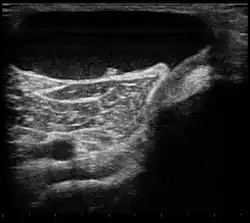

Ultrasound image of Baker's cyst

Diagnosis is by examination. A Baker's cyst is easier to see from behind with the patient standing with knees fully extended. It is most easily palpated (felt) with the knee partially flexed. Diagnosis is confirmed by ultrasonography, although if needed and there is no suspicion of a popliteal artery aneurysm then aspiration of synovial fluid from the cyst may be undertaken with care. An MRI image can reveal presence of a Baker's cyst.